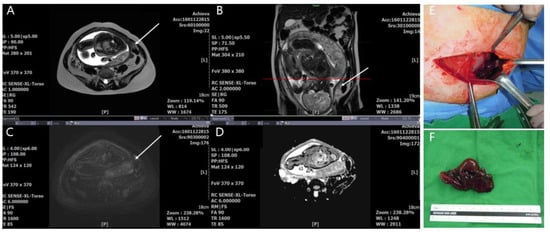

4.5. MRI Findings by a Multiparameter Imaging